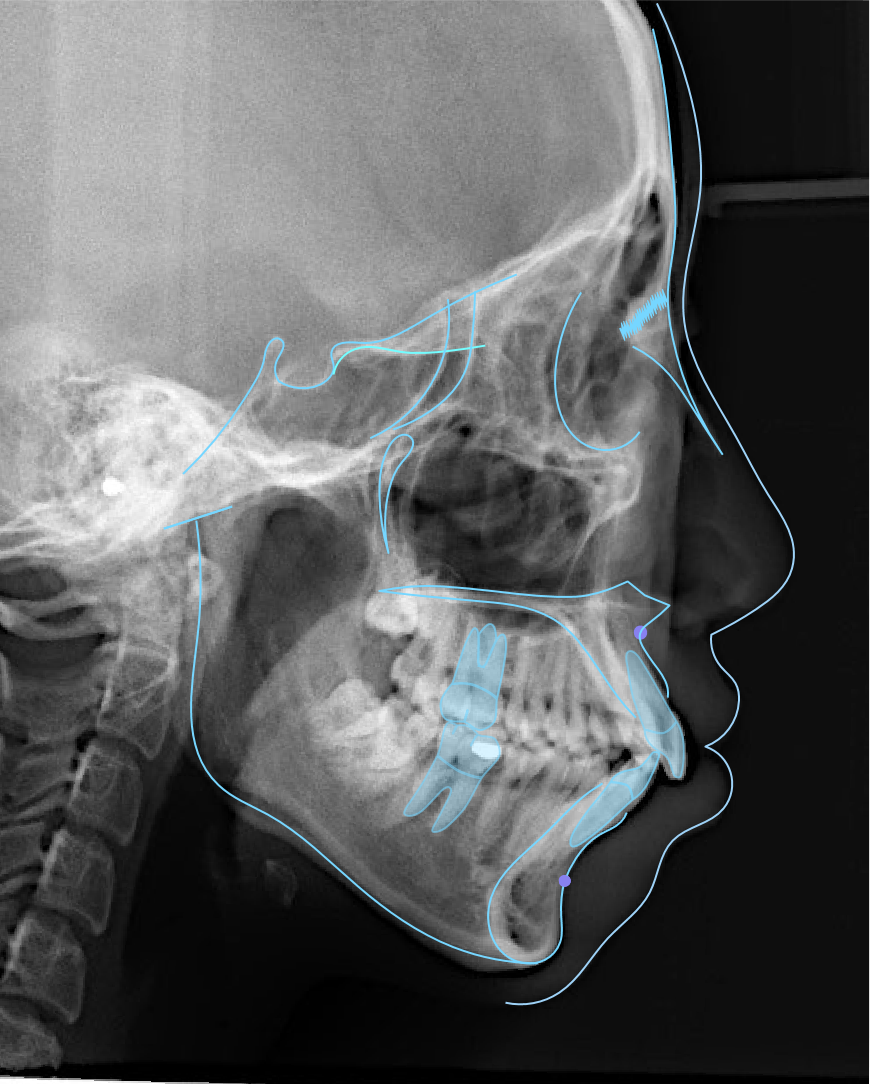

_PRE-TXNorm FMIA°47°55.0SNA°77.7°83.0SNB°70.2°80.0ANB°7.5°3.0FMA° 29.826PFH/AFH70.5°70Z Angle°50.3°77U1-FH113.0110.0IMPA°103.297.0U Lip to s’ line6.3 mm5.0L Lip to s’ line3.9 mm3.0OP-FH1215

头侧位片:

▲下颌后缩,骨性Ⅱ类

▲高角,颏部发育不足

▲上下前牙唇倾

Post-TXPRE-TXPost-TXNormFMIA°47°57.555.0SNA°77.7°76.883.0SNB°70.2°73.780.0ANB°7.5°3.13.0FMA° 29.828.026PFH/AFH70.5°65.970Z Angle°50.3°64.477U1-FH113.0103.7110.0 IMPA°103.291.197.0U Lip tos’ line6.3 mm3.25.0L Lip to s’ line3.9 mm1.03.0OP-FH1212.615